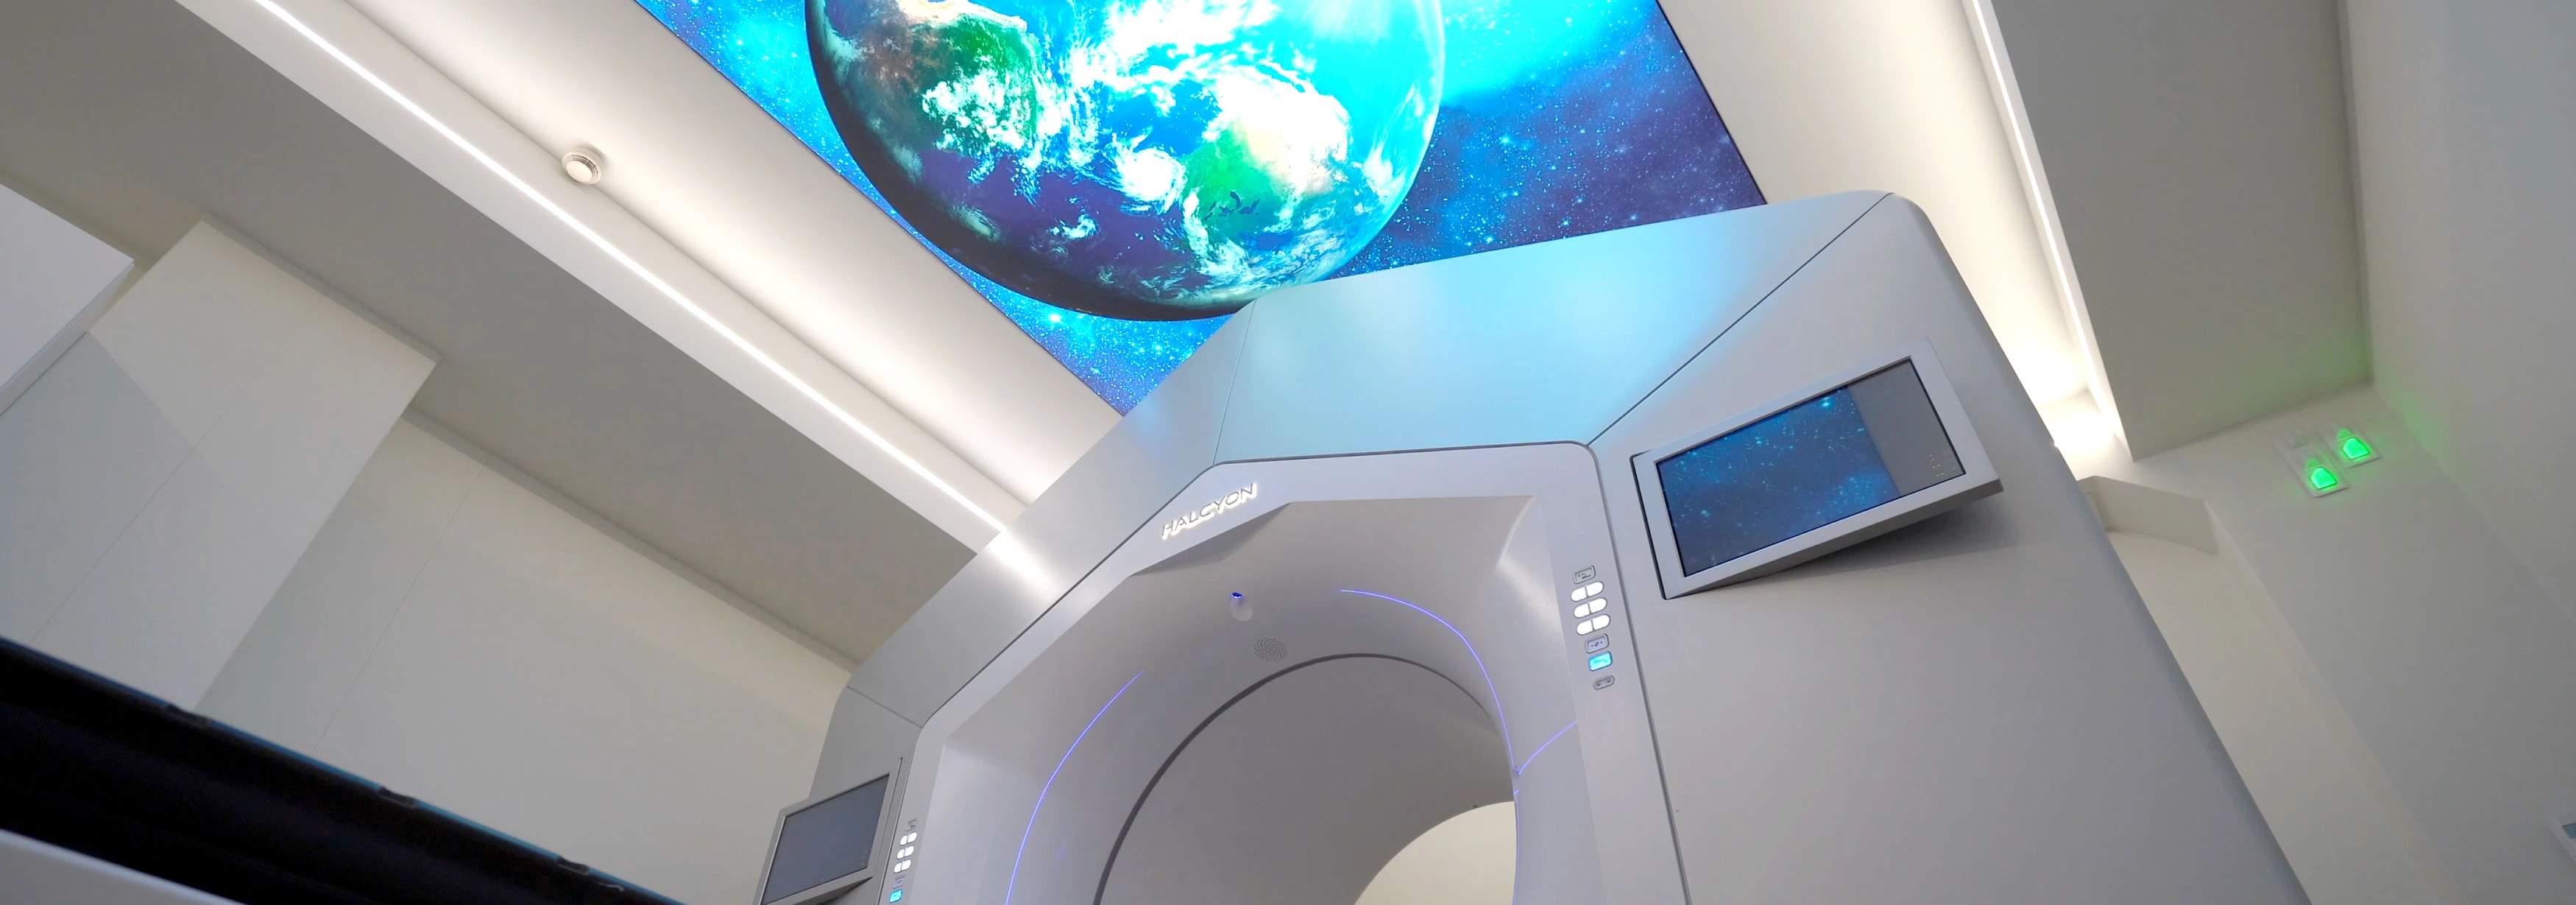

Ρομποτικό Κέντρο

στην Ελλάδα

1o

Το Metropolitan Hospital, πρωτοπόρο στις ιατρικές εξελίξεις, διαθέτει προηγμένα ρομποτικά συστήματα, όπως τα Da Vinci Xi και Mako, καθώς και μία από τις πιο έμπειρες ομάδες ρομποτικής χειρουργικής στην Ευρώπη. Κάθε χρόνο, οι εξειδικευμένοι χειρουργοί του πραγματοποιούν τη μεγαλύτερη σειρά ουρολογικών ρομποτικών επεμβάσεων σε ευρωπαϊκό επίπεδο.

Τεχνολογία αιχμής στα χέρια έμπειρων γιατρών